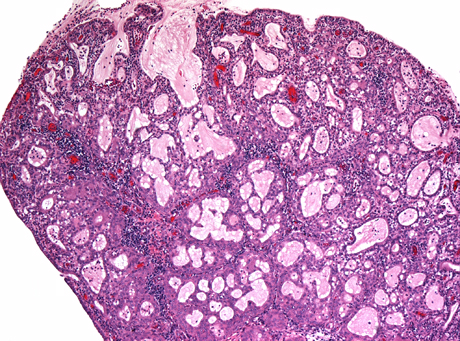

Nabothian cyst

Normal finding caused by obstruction of crypt opening by squamous epithelium thus dilating endocervical glands

- usually superificial but can go deep

- can cause acute/chronic cervicitis

Micro: uniform architecture, no stratification, mits, or atypia

- can cause reactive changes if rupture

Nabothian cysts